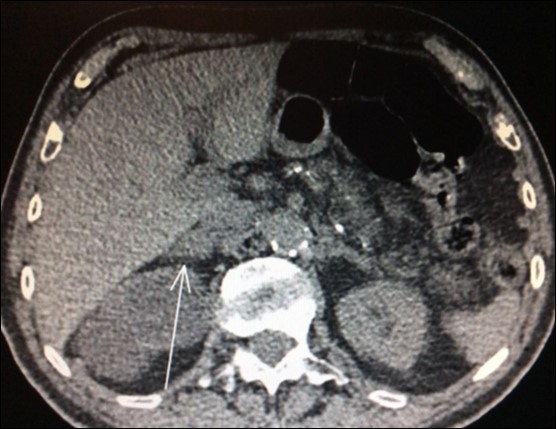

Nevertheless, in another study, only 28 out of 39 (71.8%) patients who underwent adrenalectomy for suspect adrenal tumor by FDG-PET/CT confirmed metastasis. Ten of those were benign adenoma and one was a non-functional pheochromocytoma29. Thus, FDG-PET/CT produced an unexpected high rate (28.2%) of false-positive results in this trial. Despite benign adenoma may mimicking metastasis and produce a positive preoperative FDG-PET/CT, history of primary lung malignancy and SUV max >2.65 were more commonly associated with metastasis in this paper (Figure 2).

Figure 2.PET-CT with high uptake on right adrenal